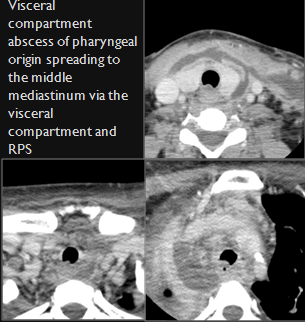

The upper lung zones and mediastinum visualized are abnormal.